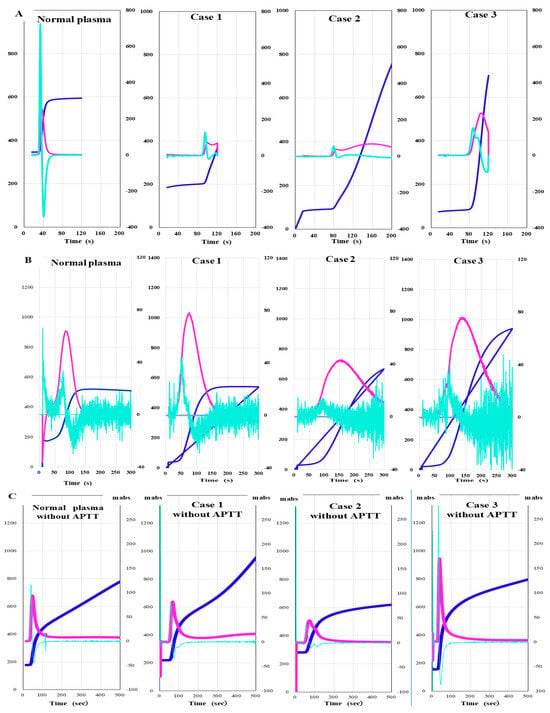

CWA-APTT was measured using patient PPP and HemosIL APTT-SP on an ACL-TOP system based on previously reported methods [29]. The CWA-small amount of tissue factor activation assay (sTF/FIXa) was performed using patient PRP and 2000-fold diluted HemosIL RecombiPlasTin 2G with saline solution including CaCl2 on an ACL-TOP® system [30]. The CWA-sTT of patient PPP was measured using an ACL-TOP® system with 0.2 IU of thrombin, which was diluted with 0.9% saline solution including CaCl2 [26,29]. CWA-sTT was measured with or without 16-fold diluted APTT-SP with 0.9% saline solution. CWA-sTT reflects thrombin burst caused by activated platelets and activated FVIII (FVIIIa), and when APTT reagent is added, it is more strongly affected by FVIIIa. In hemophilia A (HA), since the residual FVIII is extremely low, CWA-sTT is only minimally enhanced; in AiFVIIID, in comparison, it shows mild enhancement (Figure 1).

The peak time of CWA-APTT was significantly prolonged, and the peak heights of the first and second derivatives of CWA-APTT were markedly lower in cases 1, 2, and 3 than in normal plasma (Figure 6A). There was no significant difference in the peak time or height of CWA-sTF/FIXa between normal plasma and case 1. The peak time of CWA-sTF/FIXa was prolonged in cases 2 and 3 (Figure 6B). In CWA-sTT without APTT reagent, the peak time was prolonged and the peak height was decreased in cases 1 and 2. In CWA- sTT with APTT reagent, the peak time was prolonged, and the peak height was decreased in cases 1–3 (Figure 6C,D).

Figure 6.

Clot waveform analysis of APTT (A), sTF/FIXa (B) and sTT without APTT reagent (C) and sTT with APTT reagent (D) in three cases of autoimmune factor VIII deficiency. APTT, activated partial thromboplastin time; sTF/FIXa, small amount of tissue factor- induced coagulation factor IX activation assay; sTT, clotting time using a small amount of thrombin; navy line, fibrin formation curve; pink line, first derivative curve (velocity); light blue, second derivative curve (acceleration). CWA-APTT was markedly abnormal in cases 1–3, CWA-STF/FIXa showed no significant difference among the 3 cases. CWA-sTT showed prolonged peak time and decreased peak height in cases 1–3 compared with normal plasma.